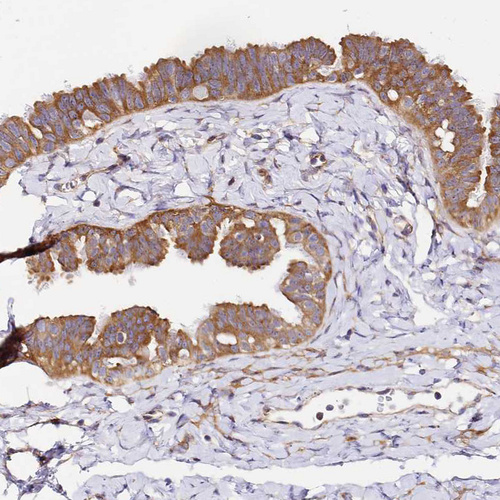

Immunohistochemical staining of human fallopian tube shows strong cytoplasmic positivity in glandular cells.